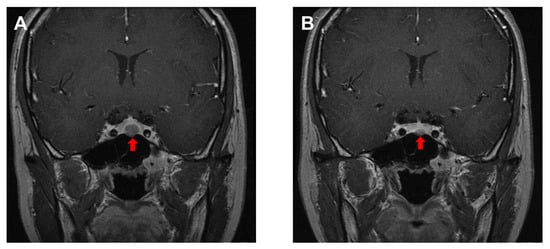

- Burlacu, M.C.; Maiter, D.; Duprez, T.; Delgrange, E. T2-weighted magnetic resonance imaging characterization of prolactinomas and association with their response to dopamine agonists. Endocrine 2019, 63, 323–331. [Google Scholar] [CrossRef]